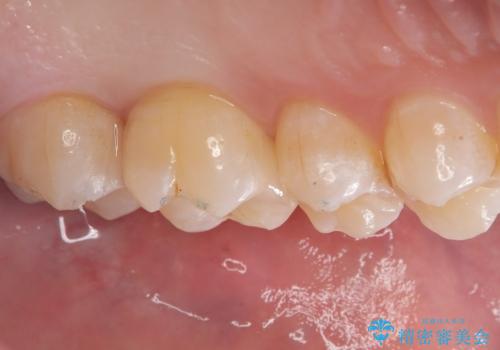

左上6番の歯には元々修復物が入っていましたが、それも一度除去し新たにMOD窩洞のセラミックインレーをセットしました。

左上7番咬合面裂溝の着色部分は今後エアフロー等を使用し落としていく予定です。

セラミックインレーセット時はラバーダム防湿を行っています。